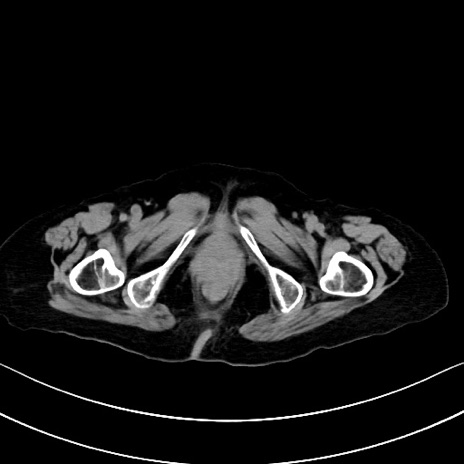

症例40(横断像)他院1日前

横断像